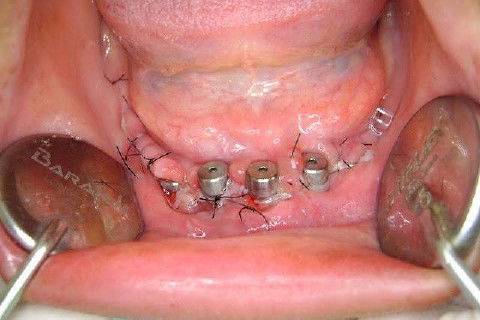

Protocolo Inferior com 5 Implantes - Parte I - Planejamento + Cirurgia

Apesar da boa adaptação e estética satisfatória, a principal queixa da paciente era a instabilidade da prótese inferior, como sempre ocorre nestes casos...atrofia do rebordo alveolar e perda da função mastigatória.